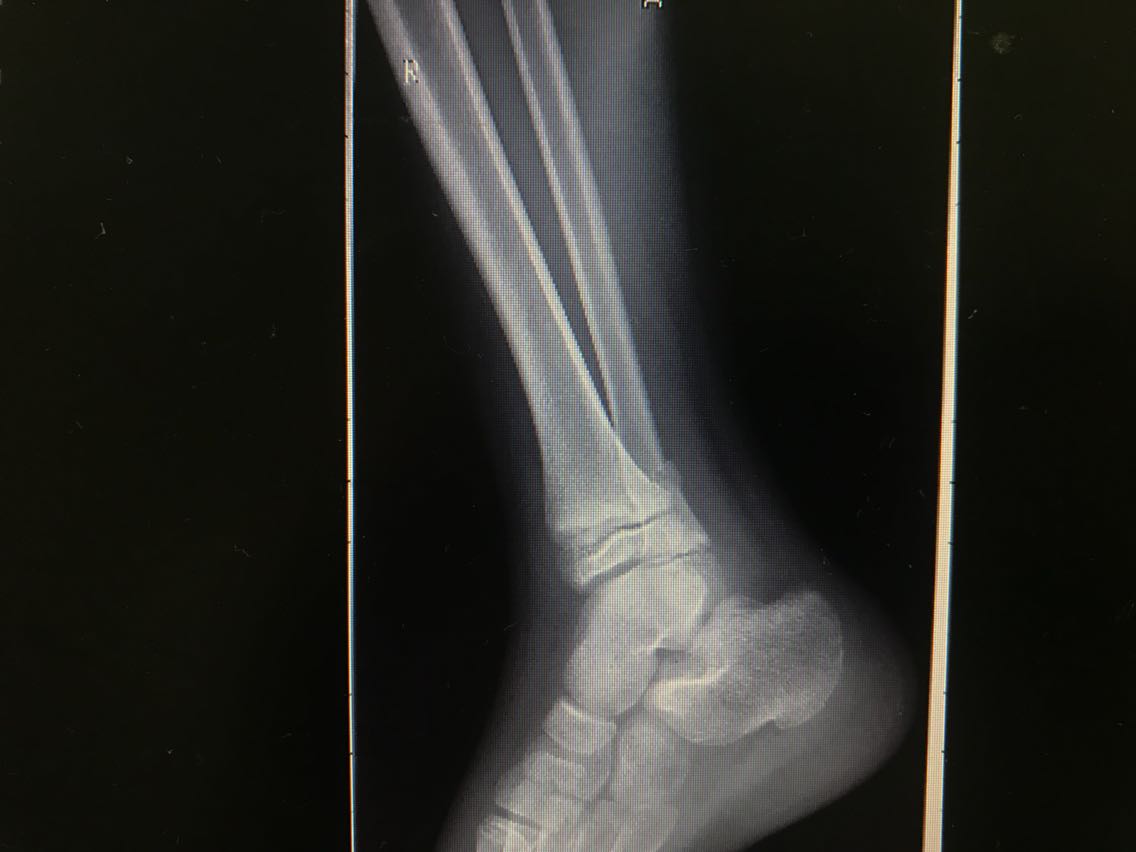

患者男性,10岁。 主诉:摔伤致右小腿疼痛,活动受限3+天 现病史:患者3+天前从高处摔下,高度约6米,摔下后右足着地。患者自述右侧小腿下段疼痛,可以耐受,意识清楚,呼之能应,无呕吐其他不适。右小腿肿胀、疼痛伴活动障碍,局部皮肤有明显青紫,无破损、流血等。遂至当地医院就诊,未予特殊处理,建议上级医院就诊。遂就诊于我院急诊科,行X线检查示:右侧腓骨下段骨折,断端稍成角、迂曲,右外踝关节间隙稍增宽,周围软组织肿胀。CT检查示:右侧腓骨下段骨折,断端稍成角、迂曲,右外踝关节间隙稍增宽,右胫骨干骺端与骺板间隙稍增宽,周围软组织肿胀。经我科医师会诊,以“右腓骨下段骨折”收入我科。患者自受伤以来精神睡眠可,食欲可,大小便正常,体重未见明显变化。 既往史无特殊。

查体:右小腿远端、足部肿胀明显,局部皮肤可见青紫,未见破损,右小腿远端皮温低,压痛不明显,桡动脉、足背动脉搏动可,右踝节活动受限,右足趾感觉、血运、活动正常,其余肢体未见明显异常。 辅助检查: X线检查,示:右侧腓骨下段骨折,断端稍成角、迂曲,右外踝关节间隙稍增宽,周围软组织肿胀。请结合临床及其它检查。右侧胫骨未见确切错位骨折征象。 CT检查,示:右侧腓骨下段骨折,断端稍成角、迂曲,右外踝关节间隙稍增宽,右胫骨干骺端与骺板间隙稍增宽,周围软组织肿胀。请结合临床及其它检查。